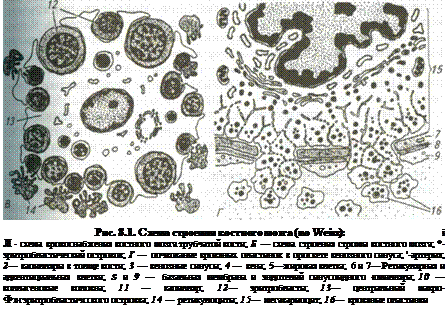

Костный мозг. У взрослых животных его подразделяют на красный и желтый, что обусловлено разной структурой содержимого мозга' в первом в большом количестве присутствуют эритроциты, во втором преобладают жировые клетки. Красный костный мозг (medullaossiumrubra). Он располагается в губчатом веществе костей свода черепа, ребер, грудины, в телах позвонков в гребне подвздошной кости, а также в эпифизах трубчатых костей и пред.! ставлен миелоидной тканью, состоящей из трехмерной сети клеток ретикулярной ткани (textusreticularis), ретикулярных и коллагеновых волокон формирующих строму, а также клеток крови, находящихся на различных стадиях развития (рис. 8.1, см. также цв. вклейку). Миелоидная ткань локализуется в костных полостях между костными перекладинами. Она образована сетью ретикулярных клеток, между которыми обнаруживают большое количество тонкостенных фенест-рированных синусоидных капилляров (vascapillaresinusoideum). Через стенки последних новообразованные клетки крови поступают в общий кровоток. В миелоидной ткани находится основная популяция стволовых кроветворных клеток (СКК), являющихся родоначальниками трех самостоятельных линий форменных элементов крови: эритроцитопо-этической, гранулоцитопоэтической и мегакариоцитарно-тромбоци-топоэтической. В ней проходят начальные стадии развития популяции Т- и В-лимфоцитов. Среди гемопоэтических клеток красного костного мозга выделяют: стволовые и полустволовые клетки, морфологически сходные с малыми лимфоцитами и трудно идентифицируемые обычными гистологическими методами; властные формы (проэритробласты, промиело-циты, метамиелоциты, пролимфоциты, промоноциты, мегакари-областы, мегакариоциты); дифференцирующиеся и зрелые форменные элементы крови. Соотношение зрелых и незрелых форм в красном костном мозге и в периферической крови служит важным диагностическим показателем нормы или патологии. В норме в кровоток из красного костного мозга попадают только зрелые форменные элементы крови и некоторое количество клеток, мигрирующих в другие органы, например, в лимфоидные. Гемопоэтические клетки, как правило, образуют островки, локализующиеся между синусоидными капиллярами. Эритробласты в процессе созревания формируют розетки вокруг макрофага, содержащего в цитоплазме железо, которое используется эритробластами для синтв' за гемоглобина. Другая функция макрофагов — поглощение выталкиваемых из нормоцитов ядер. Клетки эритробластического ряда — проэритробласты (proerythro-blastus) характеризуются округлым или овальным ядром с мелким диффузным хроматином, крупным ядрышком и слегка базофильной цитоплазмой. Располагаются проэритробласты в очажке небольшими группами и после интенсивной пролиферации превращаются в более мелкие клетки с резко базофильной цитоплазмой — базофильные э Ритробласты (erythroblastusbasophilicus), тоже интенсивно размножающиеся. По мере синтеза гемоглобина цитоплазма клеток начинает воспринимать кислые красители — клетки превращаются в полих матофильные эритробласты (etythtroblastuspolichromathophilicus) в paxпоследних ядрышко отсутствует, но они продолжают активно xi*' лиферировать. После дифференцировки и накопления гемоглоби°" клетки переходят в стадию оксифильных эритробластов (erythrobla^ acidophilicus), теряют способность к размножению, ядра в них пикн тизируются и элиминируются из клетки. Клетка превращается вначал" в ретикулоцит, а затем в зрелый эритроцит. Продолжительность жизн эритроцитов в периферической крови, например, у свиньи составчЯе ! в среднем 70 дней, у крупного рогатого скота и овцы 50...60. В амоп/ ном веществе островков эритропоэза преобладают гликопротеиды ко личество которых уменьшается по мере созревания клеток и увеличе" ния их подвижности. Между эритроидными островками встречаются дифференцирую.-щиеся клетки гранулоцитарного ряда (базофилы, эозинофилы, нейт-рофилы), а также группы жировых клеток. В островках миело- или гранулоцитопоэза в аморфном веществе преобладают протеогликаны количество которых уменьшается по мере созревания клеток. В процессе пролиферации и дифференцировки уменьшаются размеры миелоидных клеток, изменяется форма их ядер — от округлой до сегментированной, в цитоплазме накапливается специфическая зернистость. Общая продолжительность жизни нейтрофильных гранулоци-тов4...8 дней, эозинофилов 8... 12 дней, а лимфоцитов 10...15 дней. Кровяные пластинки образуются в результате фрагментации цитоплазмы на отдельные участки особых гигантских полиплоидных клеток — мегакариоцитов, тесно контактирующих со стенкой синусоид-ных капилляров. Наиболее трудно идентифицировать (наряду со стволовыми и полустволовыми предшественниками) костномозговые лимфоидные элементы (предшественники Т- и В-лимфоцитов и моноцитов), чаще встречающиеся вблизи капилляров. Наиболее интенсивное кроветворение отмечают вблизи эндоста, где концентрация стволовых клеток втрое выше, чем в центре костномозговой полости. Желтый костный мозг (medullaossiumflava). Он находится в диафи-зах трубчатых костей и представлен преимущественно жировыми клетками, содержащими пигменты типа липохромов. Небольшое количество адипоцитов постоянно встречается и в красном костном мозге. Тимус (зобная, или вилочковая, железа). В тимусе {thymus) происходит антигеннезависимая, генетически запрограммированная пролиферация и дифференцировка Т-лимфоцитов из Т-предшествеников (прекурсоров), мигрирующих из красного костного мозга. Тимус контролирует все иммунные реакции. Орган появляется в эмбриогенезе достаточно рано. Источником его развития служит эпителий, прорастающий в виде трубок в подлее' щую мезенхиму из 3-го и 4-го жаберных карманов. Эпителиальна* адка инфильтрируется лимфоцитами. Таким образом, в плане раз-за1СЛ я и тканевого строения, тимус представляет собой лимфоэпители-ВИТ нЫЙ орган, относящийся к группе бранхиогенных желез. Эпители- ная основа органа проявляет черты эндокринной железы особенно ^ко в период внутриутробной жизни. Тимус покрыт соединительнотканной капсулой, продолжающейся перегородки, содержащие сосуды и разделяющие доли железы на не-В лно отграниченные дольки. В зависимости от вида животного коли-П °ство долей в тимусе варьирует: у жвачных и свиньи железа состоит из Ч !ух долей — грудной непарной и шейной парной; у лошади и собаки щейная часть тимуса развита слабо или вовсе отсутствует, а развита только грудная непарная часть. Долька состоит из трехмерной сети отросчатых эпителиоретикуляр-ньгх клеток, образующих строму органа. В петлях сети располагаются лимфоциты (тимоциты). В каждой дольке выделяют корковое и мозговое вещество. Их соотношение может меняться в зависимости от функционального состояния иммунной системы. В корковом веществе дольки сконцентрировано большое количество лимфоцитов, плотно прилегающих друг к другу, что придает ему более темную окраску на гистологических срезах. Мозговое вещество выглядит более светлым из-за того, что в нем существенно меньше лимфоцитов и на их фюне выделяются ретикулоэпителиальные клетки и тимусные тельца, или тельца Гассаля (рис. 8.2). В корковом веществе выделяют субкапсулярную зону, где находятся крупные лимфоидные клетки — лимфобласты, или предшественники Т-лимфоцитов, мигрирующие сюда из красного костного мозга. Под влиянием гемопоэтических факторов, выделяемых эпителиальными ретикулоцитами, лимфобласты активно пролиферируют и превращаются в Т-лимфоциты, часть из которых переходит во внутреннюю зону коры, где они продолжают активно размножаться, дифференцируются, приобретая один из маркеров Т-клеток (Т-киллер, Т-хелпер, Т-суп-рессор), затем зрелые клетки перемещаются в мозговое вещество. Эпителиоретикулярным клеткам свойственно овальное или округлое крупное светлое ядро с 2...3 ядрышками. В цитоплазме выявляют комплекс Гольджи, мелкие митохондрии, фрагменты ГлЭПС и секреторные вакуоли диаметром 0,5... 1,5 мкм. Своими отростками указанные клетки охватывают тимоциты, создавая микроокружение, необходимое для их деления и созревания. В корковом веществе различает: эпителиоретикулоциты следующих типов: секреторные клетки, вырабатывающие биологически активные вещества, необходимые для с °зревания тимоцитов; «клетки-няньки», включающие в свою цитоплазму до нескольких десятков тимоцитов, изолируя их от окружающей среды и, по-видимому, участвуя в их селекции; периваскулярные ^тки, охватывающие своими отростками сосуды и участвующие в Формировании гемато-тимического барьера.